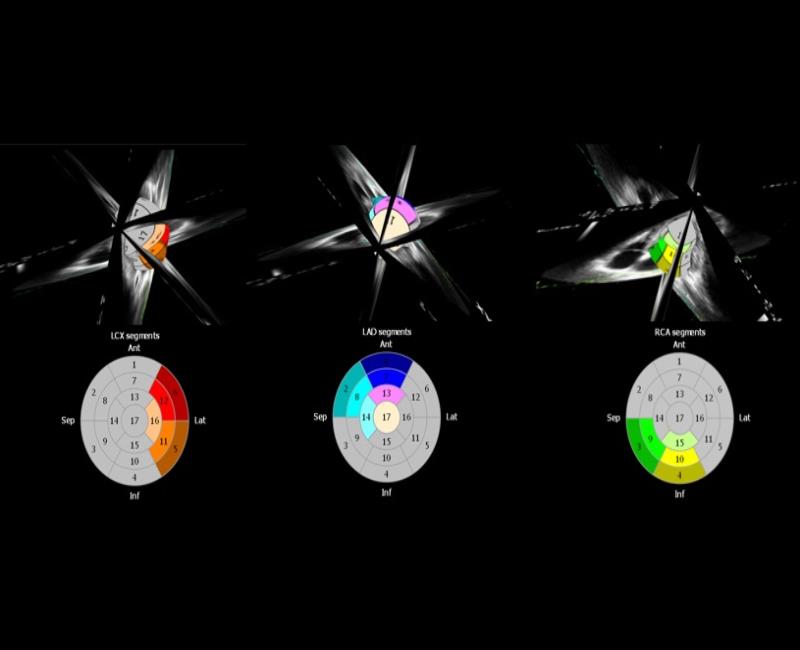

Siêu âm tim mạch

Xstrain4D - Đánh giá vận động vùng tâm thất trái toàn diện với Siêu âm đánh dấu mô cơ tim 4 chiều.

may sieu am mylab x7

Siêu âm đánh dấu mô theo 3 hướng: dọc, vòng tròn và xuyên tâm với công nghệ độc quyền và chính xác.